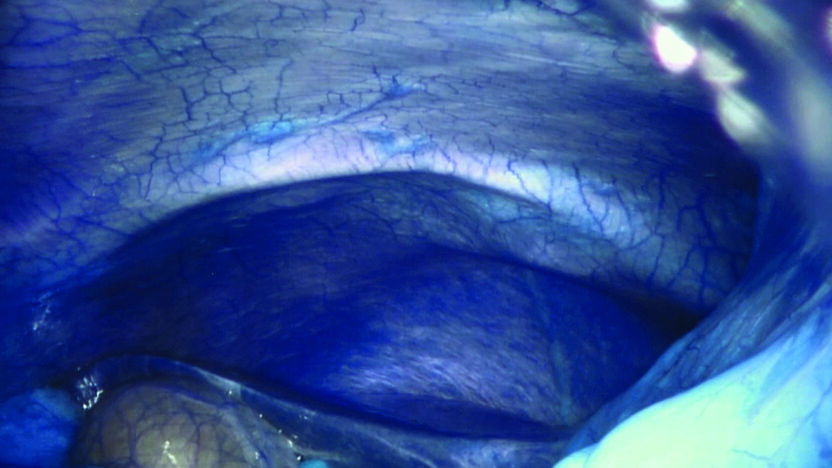

Dit laatste deel van Ancarani’s trilogie speelt zich af in een operatiekamer, waar een wonderlijke reis door het lichaam wordt gemaakt, uitgevoerd door robotarmen met de chirurg achter een soort joystick. Het geheel roept sciencefictionachtige associaties op met Fantastic Voyage (1966). Ancarani brengt de hele operatie, wonderschoon uitgelicht (zonder bloederige effecten), als een duizelingwekkende choreografie met minuscule precisie in beeld, met bijzonder spannende soundtrack.